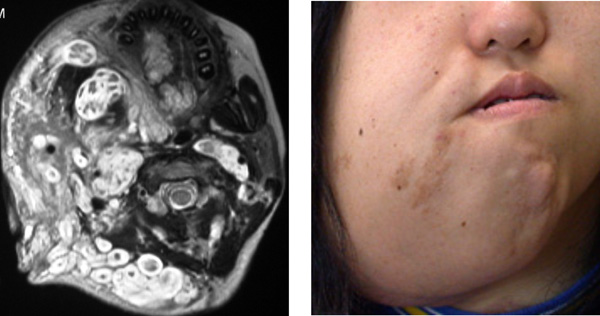

下顎部から咽頭にできた叢状神経線維腫 plexiform neurofibroma です。外から見ると大きな塊のように見えるのですが,無数の小さな神経の腫瘍が集まってできたものです。一つ一つは神経に沿って蔓のように長く伸びているので蔓状と言います。